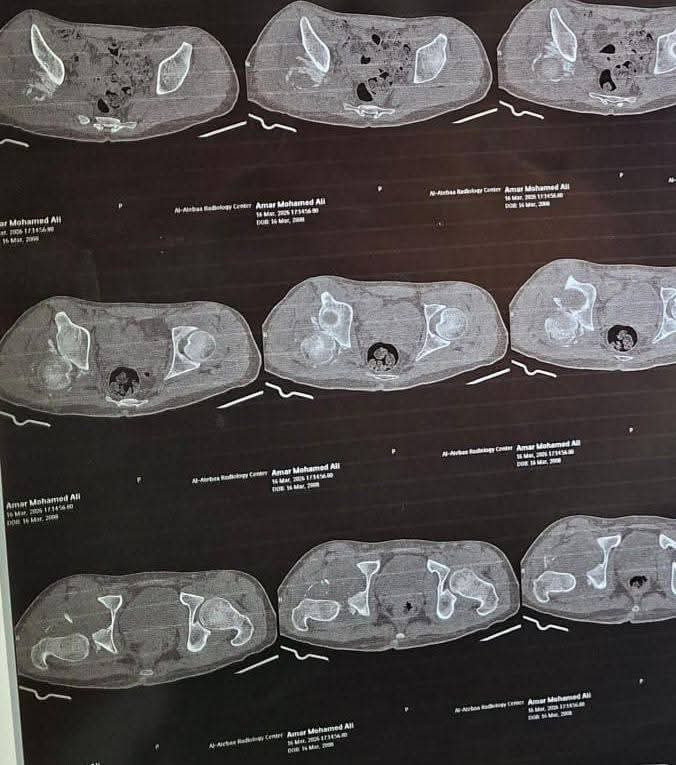

نجح فريق قسم جراحة العظام بمستشفى كفر الشيخ الجامعي في إجراء عملية جراحية دقيقة ومعقدة تُعد من الحالات النادرة، لمريض كان يعاني من كسر مهمل بالجدار الخلفي للحق الحرقفي مصحوب بخلع مزمن بمفصل الفخذ وتأثر بالعصب الوركي.

وتعود تفاصيل الحالة إلى استقبال مستشفى كفر الشيخ الجامعي لمريض يعاني من آلام شديدة بمنطقة الحوض مع سقوط جزئي بالقدم، وذلك بعد مرور شهرين على تعرضه لحادث، وبإجراء الفحوصات والأشعة اللازمة تبين وجود خلع مهمل بمفصل الفخذ مصحوب بكسر في الجدار الخلفي للحق الحرقفي.

وعلى الفور، تم تجهيز الحالة وإدخالها إلى غرفة العمليات، حيث نجح الفريق الطبي في استكشاف وتحرير العصب الوركي، وإجراء رد مفتوح للخلع، وإزالة التعظم بالأنسجة المحيطة، مع إعادة بناء الجدار الخلفي للحق باستخدام رقعة عظمية من داخل عظام الحوض، وتثبيت الكسر باستخدام الشرائح والمسامير، لتكلل العملية بالنجاح ويخرج المريض بحالة مستقرة ونتائج متميزة.